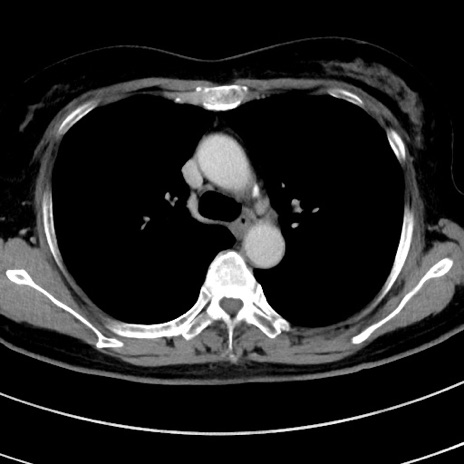

症例9(横断像)

【症例】 60歳代女性

【主訴】むかつき、みぞおちの痛み

【現病歴】3日前よりむかつきがあり、食事がとれない。

【既往歴】糖尿病

【身体所見】発熱なし、心窩部圧痛軽度あるも、腹膜刺激症状なし。

【データ】WBC 7400、CRP 1.92